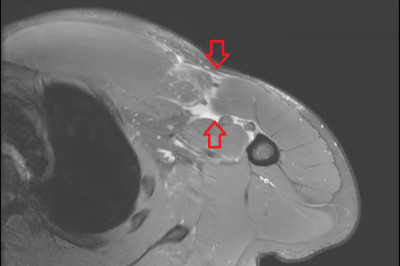

骨科醫師何承翰提醒,年長者及慢性病患者在活動改變、活動量上升的情況下,易因地面濕滑、疲勞或踩空而發生跌倒意外。(市立聯醫提供)

何承翰指出,春節前後,常見長輩因打掃、貼春聯或搬運年貨時不慎跌倒,導致手腕、足踝、髖部或脊椎骨折,相關傷勢影響日常生活自理能力,嚴重者甚至可能需要長期臥牀,進而增加肺炎、血栓等併發症風險,對身心健康有長遠影響。

何承翰表示,如民眾跌倒後出現明顯疼痛、腫脹、變形或無法支撐體重等情形,應儘速就醫檢查,把握治療黃金期。